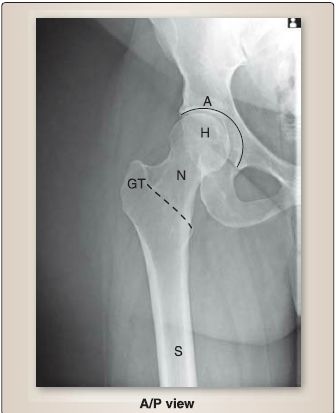

Figure 2: Plain film radiograph of normal hip (dotted line-intertrochanteric line). A = acetabulum, NP = anterior/ posterior, GT = greater trochanter, H = head, N = neck, S = shaft.